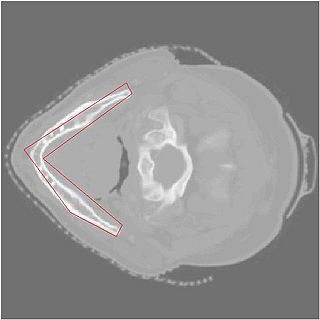

Initial Curve

• First structure of interest is the mandible, by the end of the project week, obtain its segmentation

• Segmentation results are shown above.